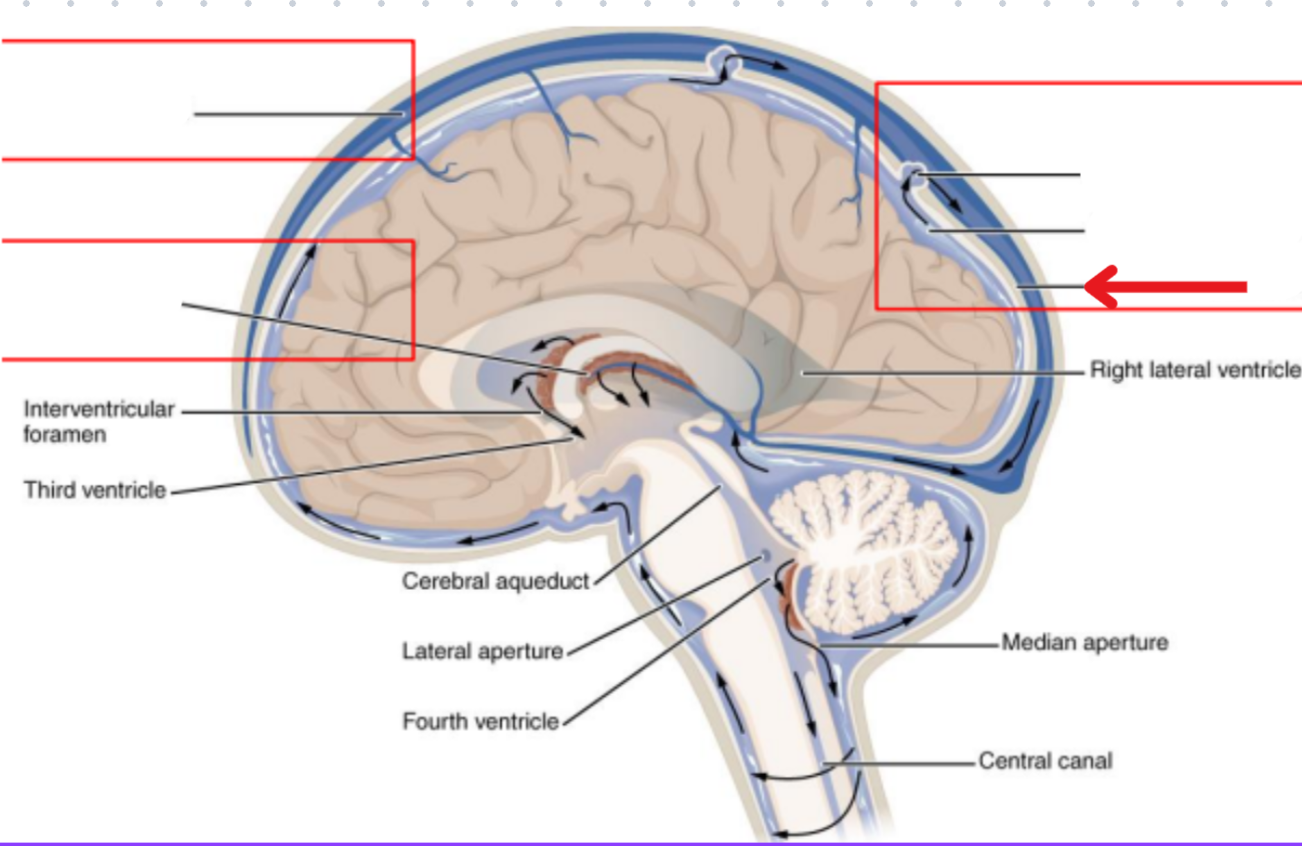

<p></p>

Cerebral hemisphere

Think of the hemispheres like paired bones

4

New cards

term image

Brainstem

5

Subdural space

6

Subarachnoid space

7

Periosteal layer of the dura mater

8

Miningeal layer of the dura mater

9

Dura mater

Makes up the fissure between the cerebral hemispheres

Merges at the corpus collosum

Thick enough to project inwards towards the brain and provide support